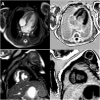

"Cases of SCMR" is a case series on the SCMR website (https://www.scmr.org) for the purpose of education. The cases reflect the clinical presentation, and the use of cardiovascular magnetic resonance (CMR) in the diagnosis and management of cardiovascular disease. The 2022 digital collection of cases are presented in this manuscript.

Keywords: Arrhythmogenic cardiomyopathy; COVID-19; Cardio-oncology; Congenital Heart disease; Coronary artery aneurysm; Hydatid disease; Hypertrophic cardiomyopathy; Metastatic disease; Myocardial. infarction; Myocarditis; Takotsubo; Vaccine associated myocarditis; Viability.